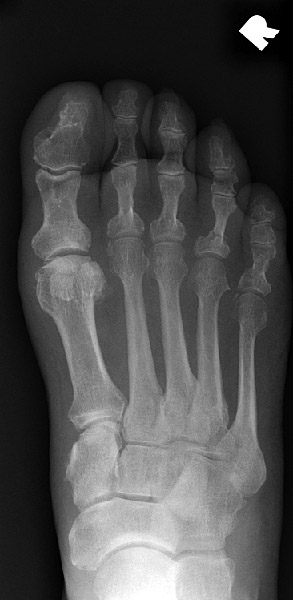

Return to Phalangeal Fracture (Foot)